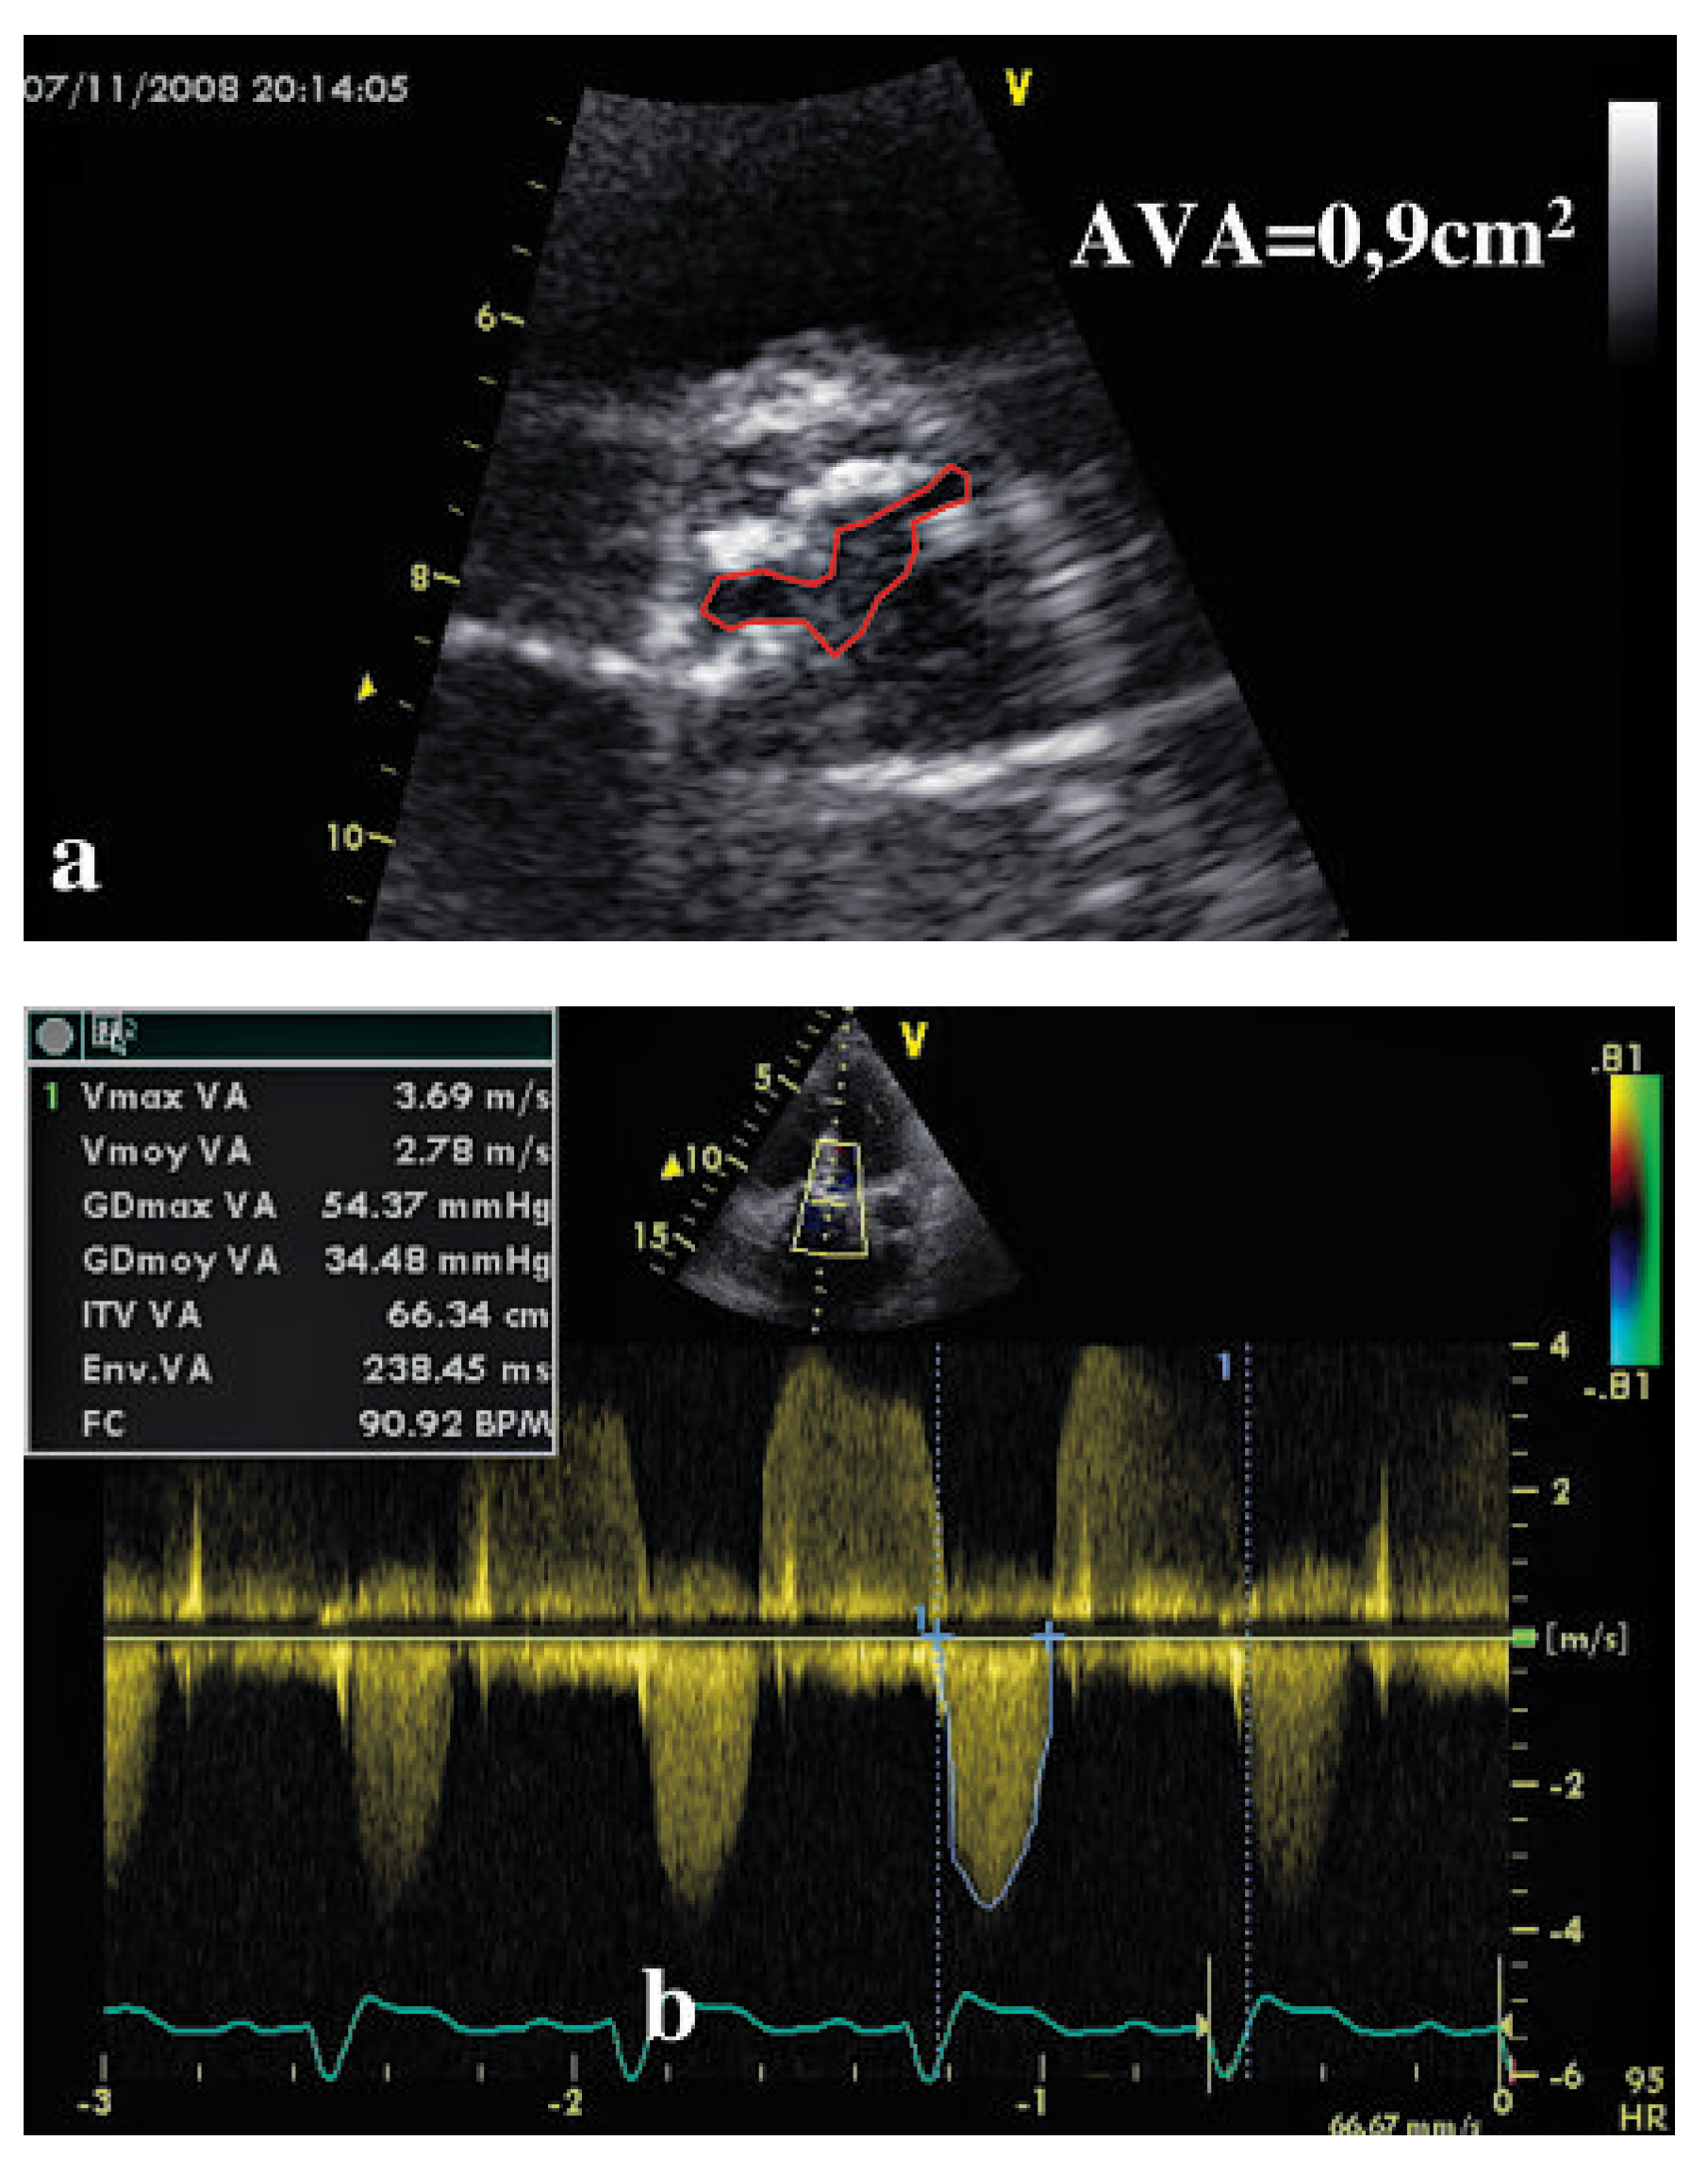

Description du cas